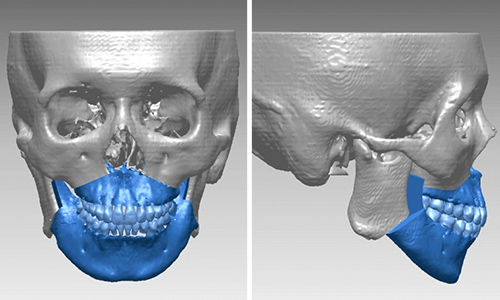

あなたのお口の中の3Dモデルを作成し、それを元に治療計画を立てます。そしてマウスピース型の矯正装置をこのように段階的に設計していきます。

矯正治療をご希望のすべての方には、治療結果の歯列をモニター上で確認できる「outcome simulator(アウトカムシミュレーター)」をお受け頂けるなど、より患者様に分かりやすい治療のご提案をしています。

日本橋はやし矯正歯科では、3Dデジタル矯正システムを応用した

マウスピース矯正での治療が可能となりました。